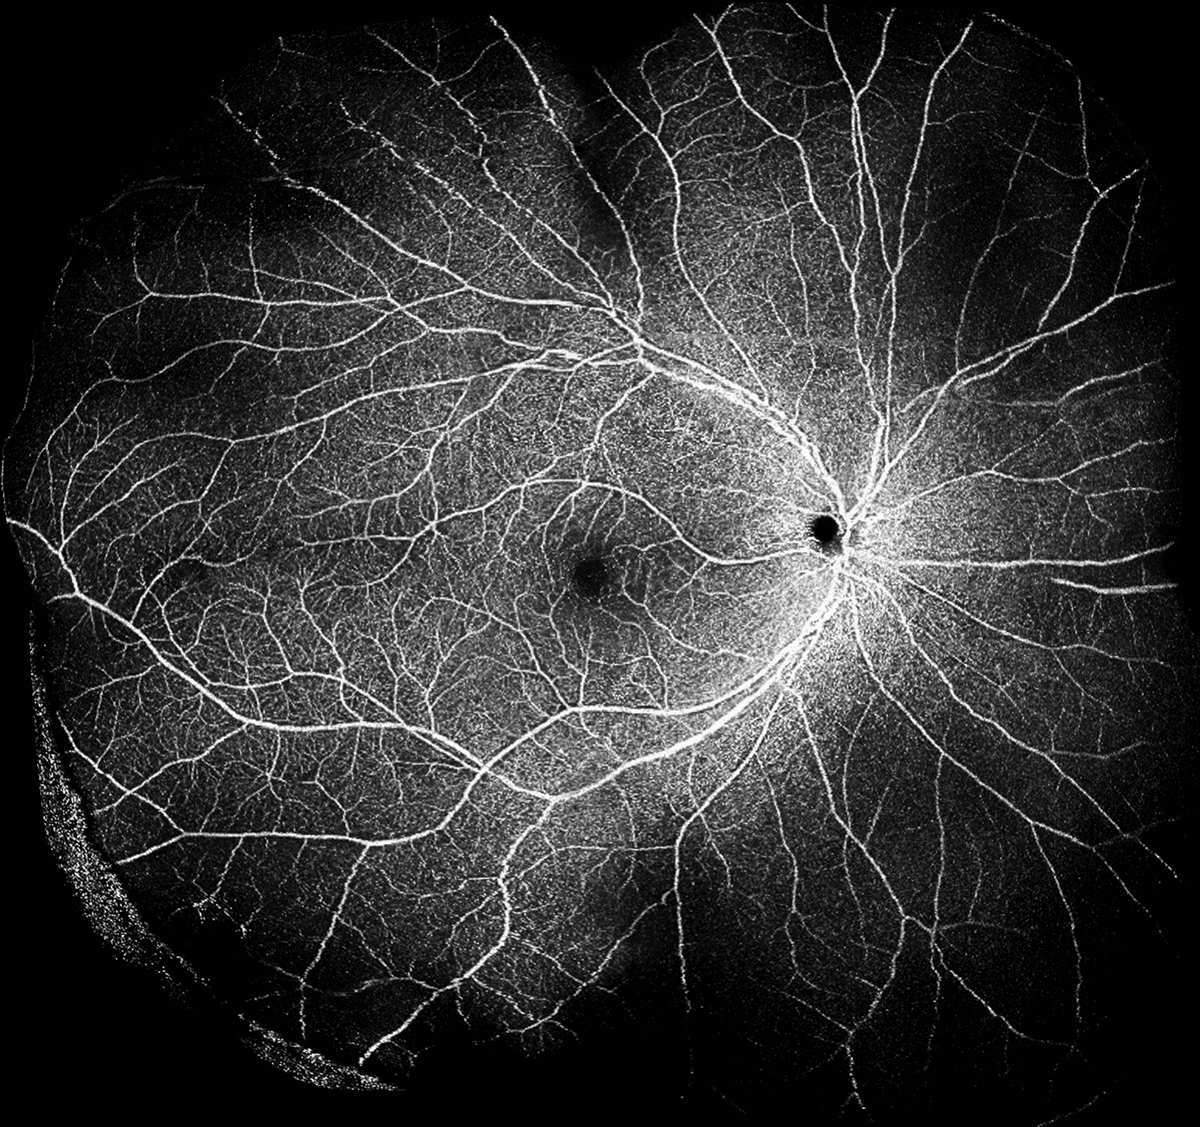

ОКТ Ангіографія з ANGIO Expert

Функція інтелектуального усунення шумів Canon на основі штучного інтелекту пропонує нову якість зображень ОКТА на основі лише одного сканування – без необхідності отримувати та об’єднувати кілька зображень. Технологія Canon Deep Learning — це революційна технологія, яка базується на величезних обсягах клінічних даних для отримання зображень із значно зменшеним шумом зображення, підвищеною деталізацією та покращеною видимістю всього за кілька секунд.